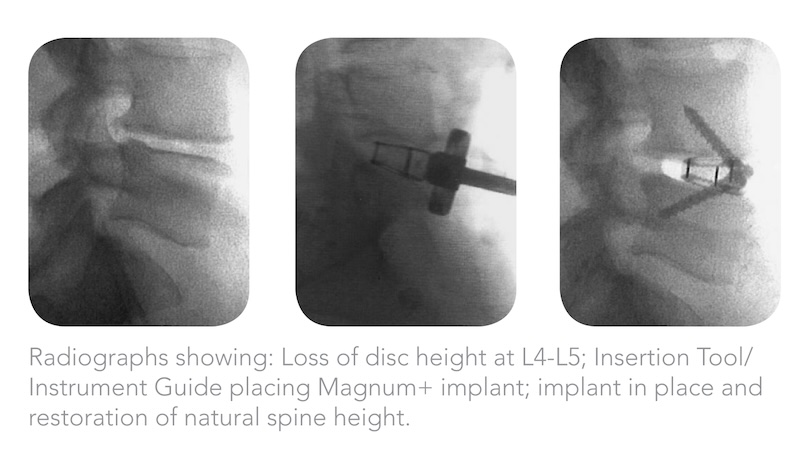

The Magnum+ Stand-Alone ALIF Spacer by Spinal Elements is a titanium coated PEEK interbody spacer using proprietary Ti-Bond surface treatment. Ti-Bond produces increased hydrophilic bonding with increased microstructure for increased surface area and bony adhesion. The spacer has integrated screw fixation with a locking ring to prevent screw backout